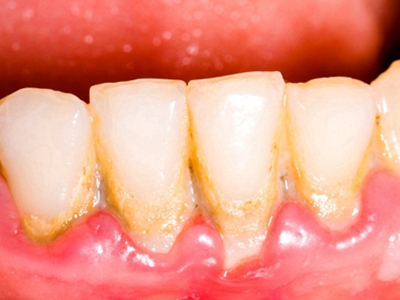

牙龈炎常见的病因是口腔卫生差,不良的口腔卫生使牙菌斑沉积于牙齿与牙龈之间,造成龈沟加深,另外牙结石、不良修复体等也可造成牙龈炎的发生。

牙龈炎患者可通过改善口腔卫生控制疾病,同时使用抗菌漱口液,如复方氯己定含漱液,并进行彻底的洁治处理。必要时,重新修整修复体的不良外形,并祛除局部刺激因素。